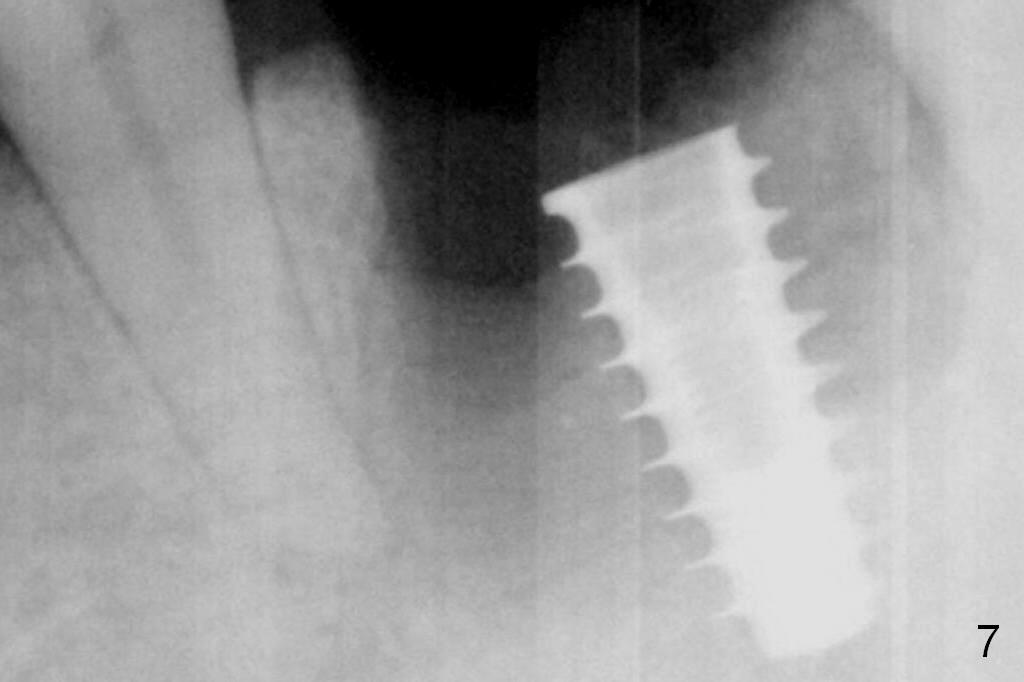

When a 5x11 mm IBS implant is being placed, the depth is tightly controlled (Fig.7). The implant is apical to the lingual crest, whereas there is ~ 2 mm implant exposure buccally clinically. That is, there is a large gap mesiobuccally, which is filled with .5-1.5 mm allograft (Fig.9 *). A 6.5x5.7(3) mm abutment (A) is placed.